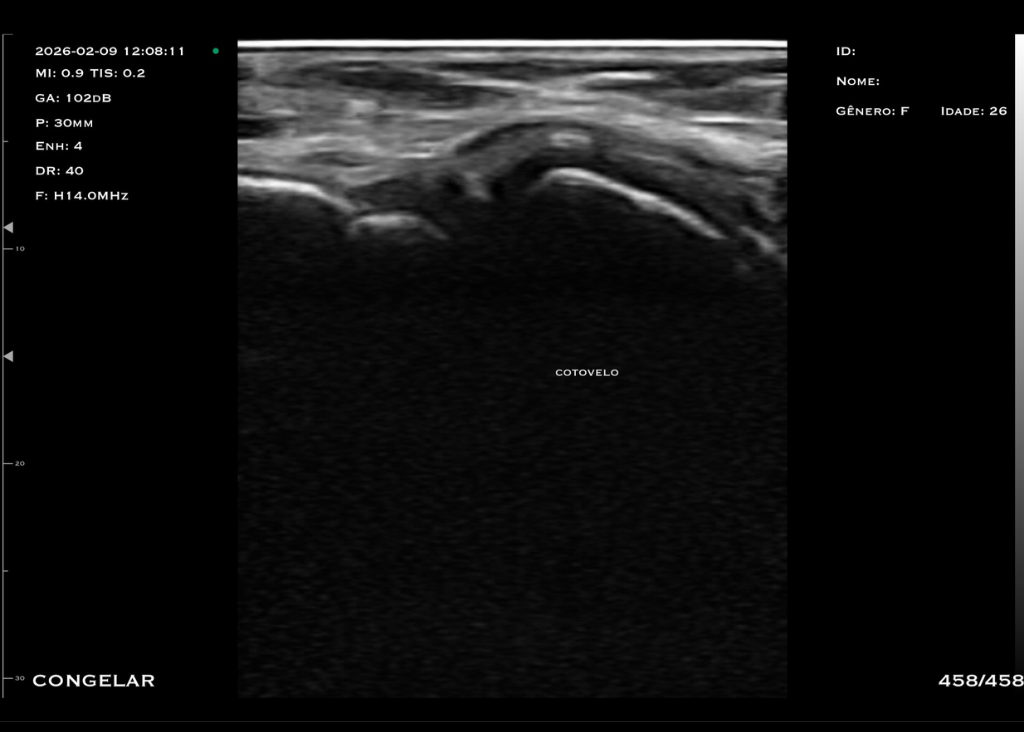

Com tecnologia linear de alta frequência (10 a 14 MHz), o modelo M4D é a escolha ideal para quem busca alta resolução em exames superficiais, com foco em detalhamento e precisão.

O trasdutor linear oferece imagens nítidas e detalhadas, permitindo a visualização precisa de estruturas como pele, tecido subcutâneo, músculos, tendões e articulações. A alta frequência garante excelente resolução para exames que exigem detalhamento extremo.

Profundidade: Até 5,5 cm

Aplicações: Visualização de articulações periféricas, avaliação de estruturas faciais, preenchedores, acesso PICC, acessos superficiais anestesia pediátrica e bloqueios periféricos.